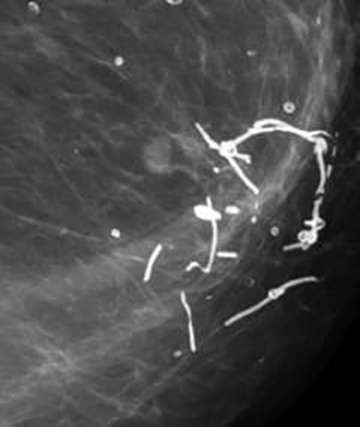

Suture Calcifications

Suture Calcifications: These represent calcium deposited within suture material, and appear linear or tubular and may outline surgical knots.